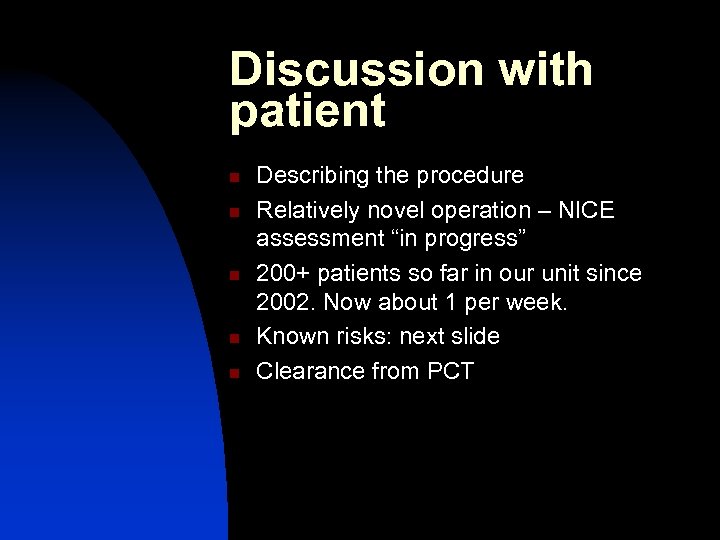

Discussion with patient n n n Describing the procedure Relatively novel operation – NICE assessment “in progress” 200+ patients so far in our unit since 2002. Now about 1 per week. Known risks: next slide Clearance from PCT

Discussion with patient n Known risks: u u u u n may not help infection requiring removal of implant electrode migration neck stiffness breakage or failure of components tethering to skin or muscle skin erosion early depletion of battery Clearance from PCT